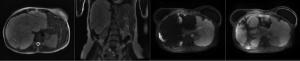

A 60-year-old woman presents with vague abdominal pain in the right upper quadrant. An ultrasound reveals a gallbladder abnormality. Based on the images from the abdomen MRI, what is the diagnosis?